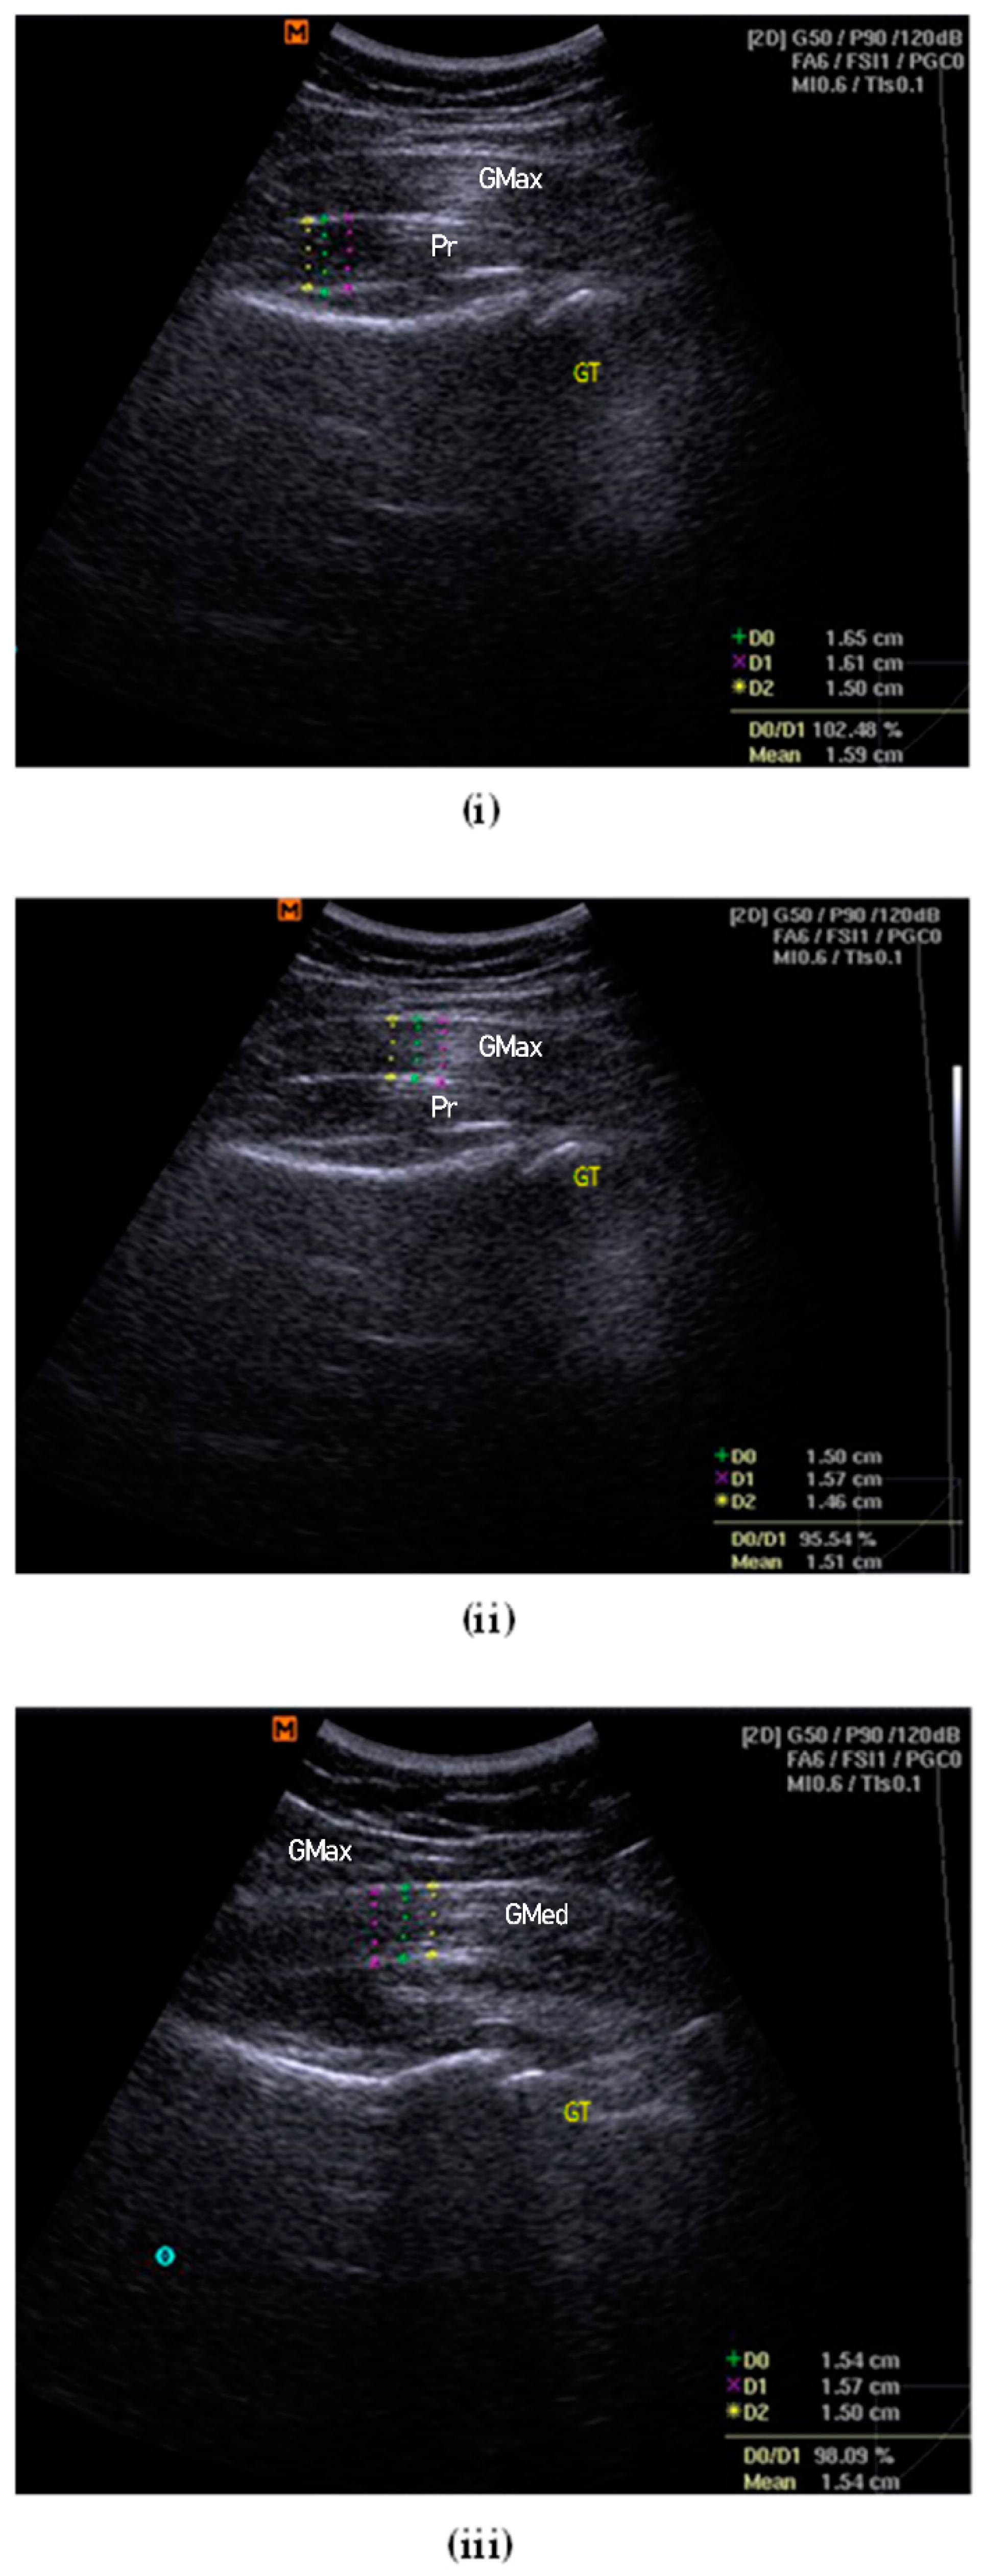

The participant was asked to perform an isometric contraction into a hip lateral rotation for several trials to assist with and confirm the identification of the piriformis muscle and fascial structures on the diagnostic USG viewscreen. The femoral greater trochanter was referred to as the main reference point, combined with the visual gliding of the piriformis muscle and the associated fasciae []. The depth and focus of the USG image were adjusted to portray the best possible image on the viewscreen. The thickness at the centre of the image was measured, considering the largest portion of muscle mass and excluding the surrounding fasciae that border the muscles []. The mean of three measurements of thickness was used for statistical analysis [] (Figure 1i).

Figure 1.

Examples of thickness measurement for piriformis (i), gluteus maximus (ii) and gluteus medius (iii). GT = greater trochanter of femur.

2.7.5. Gluteus Maximus Muscle Thickness

The participant was instructed to lie down in the prone position with both lower limbs at rest and in a neutral position. A curvilinear transducer was set at a frequency of 2.0–5.5 MHz to collect B-mode ultrasound images. During image acquisition, the transducer head was coated with a generous amount of ultrasound water-based transmission gel. The transducer was placed perpendicular to the skin and the lightest contact pressure was applied to ensure that the underlying tissues were not compressed. Measurement was taken at the first third, proximally 30%, between the PSIS and the greater trochanter of the femur []. The depth and zoom-in function were adjusted until the image of the sacrum could not be seen in the left third []. Once the best possible image was shown on the viewscreen, the image was frozen and the thickness of the gluteus maximus fibre was measured. The mean of the three measurements of thickness was used for statistical analysis [] (Figure 1ii).

2.7.6. Gluteus Medius Muscle Thickness

The participant was then instructed to lie on their side with the test leg up. The tested hip was placed in a neutral flexion/extension, neutral rotation, and at 20° of adduction (inclinometer confirmed) []. The tested knee was in full extension, with a Biofeedback® placed under the ankle and foot to ensure the resting position. A curvilinear transducer was set at 5.0 MHz (40-mm footprint; lateral and axial resolution of 1.0 and 0.93 mm, respectively) to collect bilateral anonymised resting B-mode ultrasound images []. Again, during image acquisition, the transducer head was coated with ultrasound water-based transmission gel and placed perpendicular to the skin. The lightest contact pressure was applied to ensure that the underlying tissues were not compressed. The transducer was placed midway between the proximal end of the iliac crest and the greater trochanter, approximately on the lower half of a coronal line located between the top of the greater trochanter and a point 25% of the distance between the ASIS and PSIS [,]. The cranial-caudal position of the transducer was adjusted until the superior lip of the acetabulum was one-third of the distance from the right border of the image []. The depth and zoom function were adjusted to obtain the best possible image before freezing. The thickness of the gluteus medius muscle was measured using callipers and it was considered as the distance between the inside edges of the muscle border, excluding the perimuscular fasciae. The mean of the three measurements of thickness was used for statistical analysis [] (Figure 1iii).